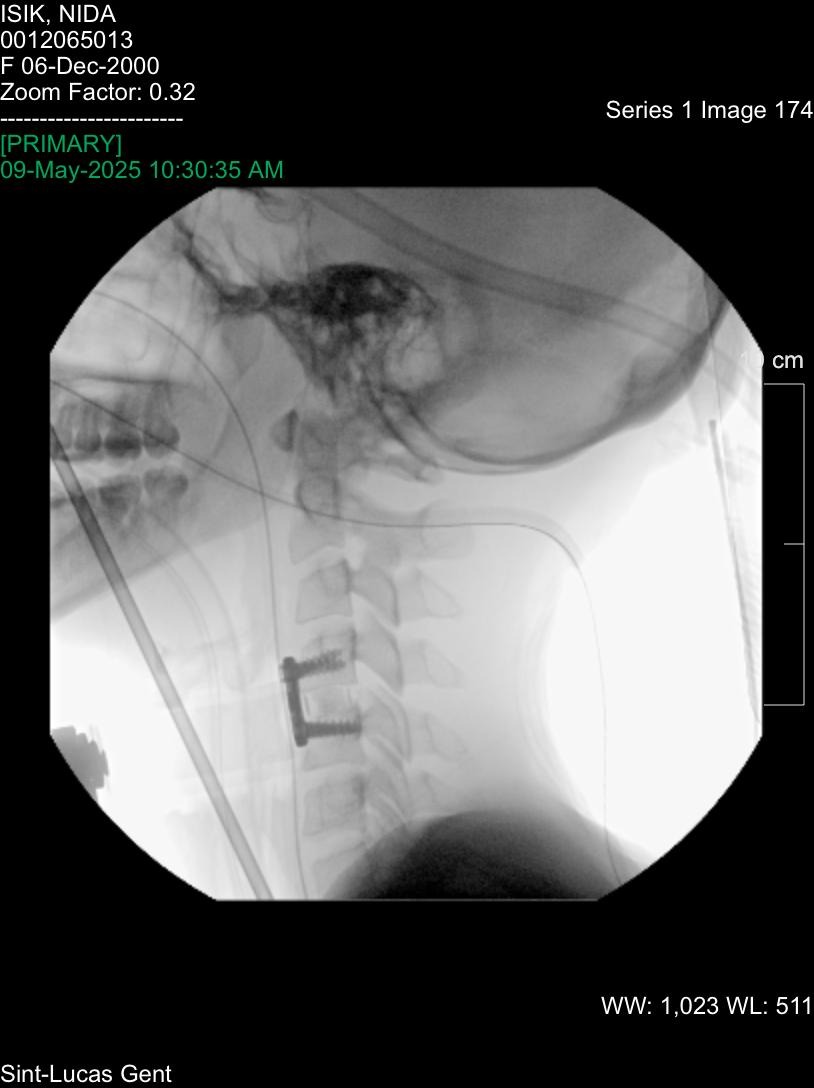

Tragically, on the very day she began preparing for the meeting, Nida suffered a serious accident. On the morning of the scheduled appointment, she fell down the stairs and sustained a severe neck injury. She experienced spinal trauma, torn ligaments, internal bleeding, and the dislocation of two vertebrae.

She underwent a highly complex and risky surgery. Initially, doctors stated that the chances of permanent paralysis were greater than her chances of survival or recovery.

Post-operative check-ups and follow-up X-rays

Future surgery on the C5-C6 vertebrae, which had to be left unoperated during the initial procedure due to her young age 24 and associated risks